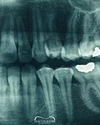

Diş implantı çevresinde diş eti iltihabı

• Periimplantitis

Fotoğraflar